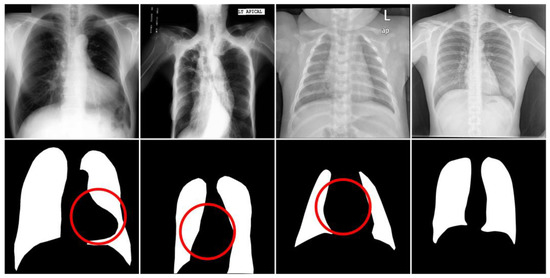

Figure 5.

Images and masks of the Shenzhen dataset.